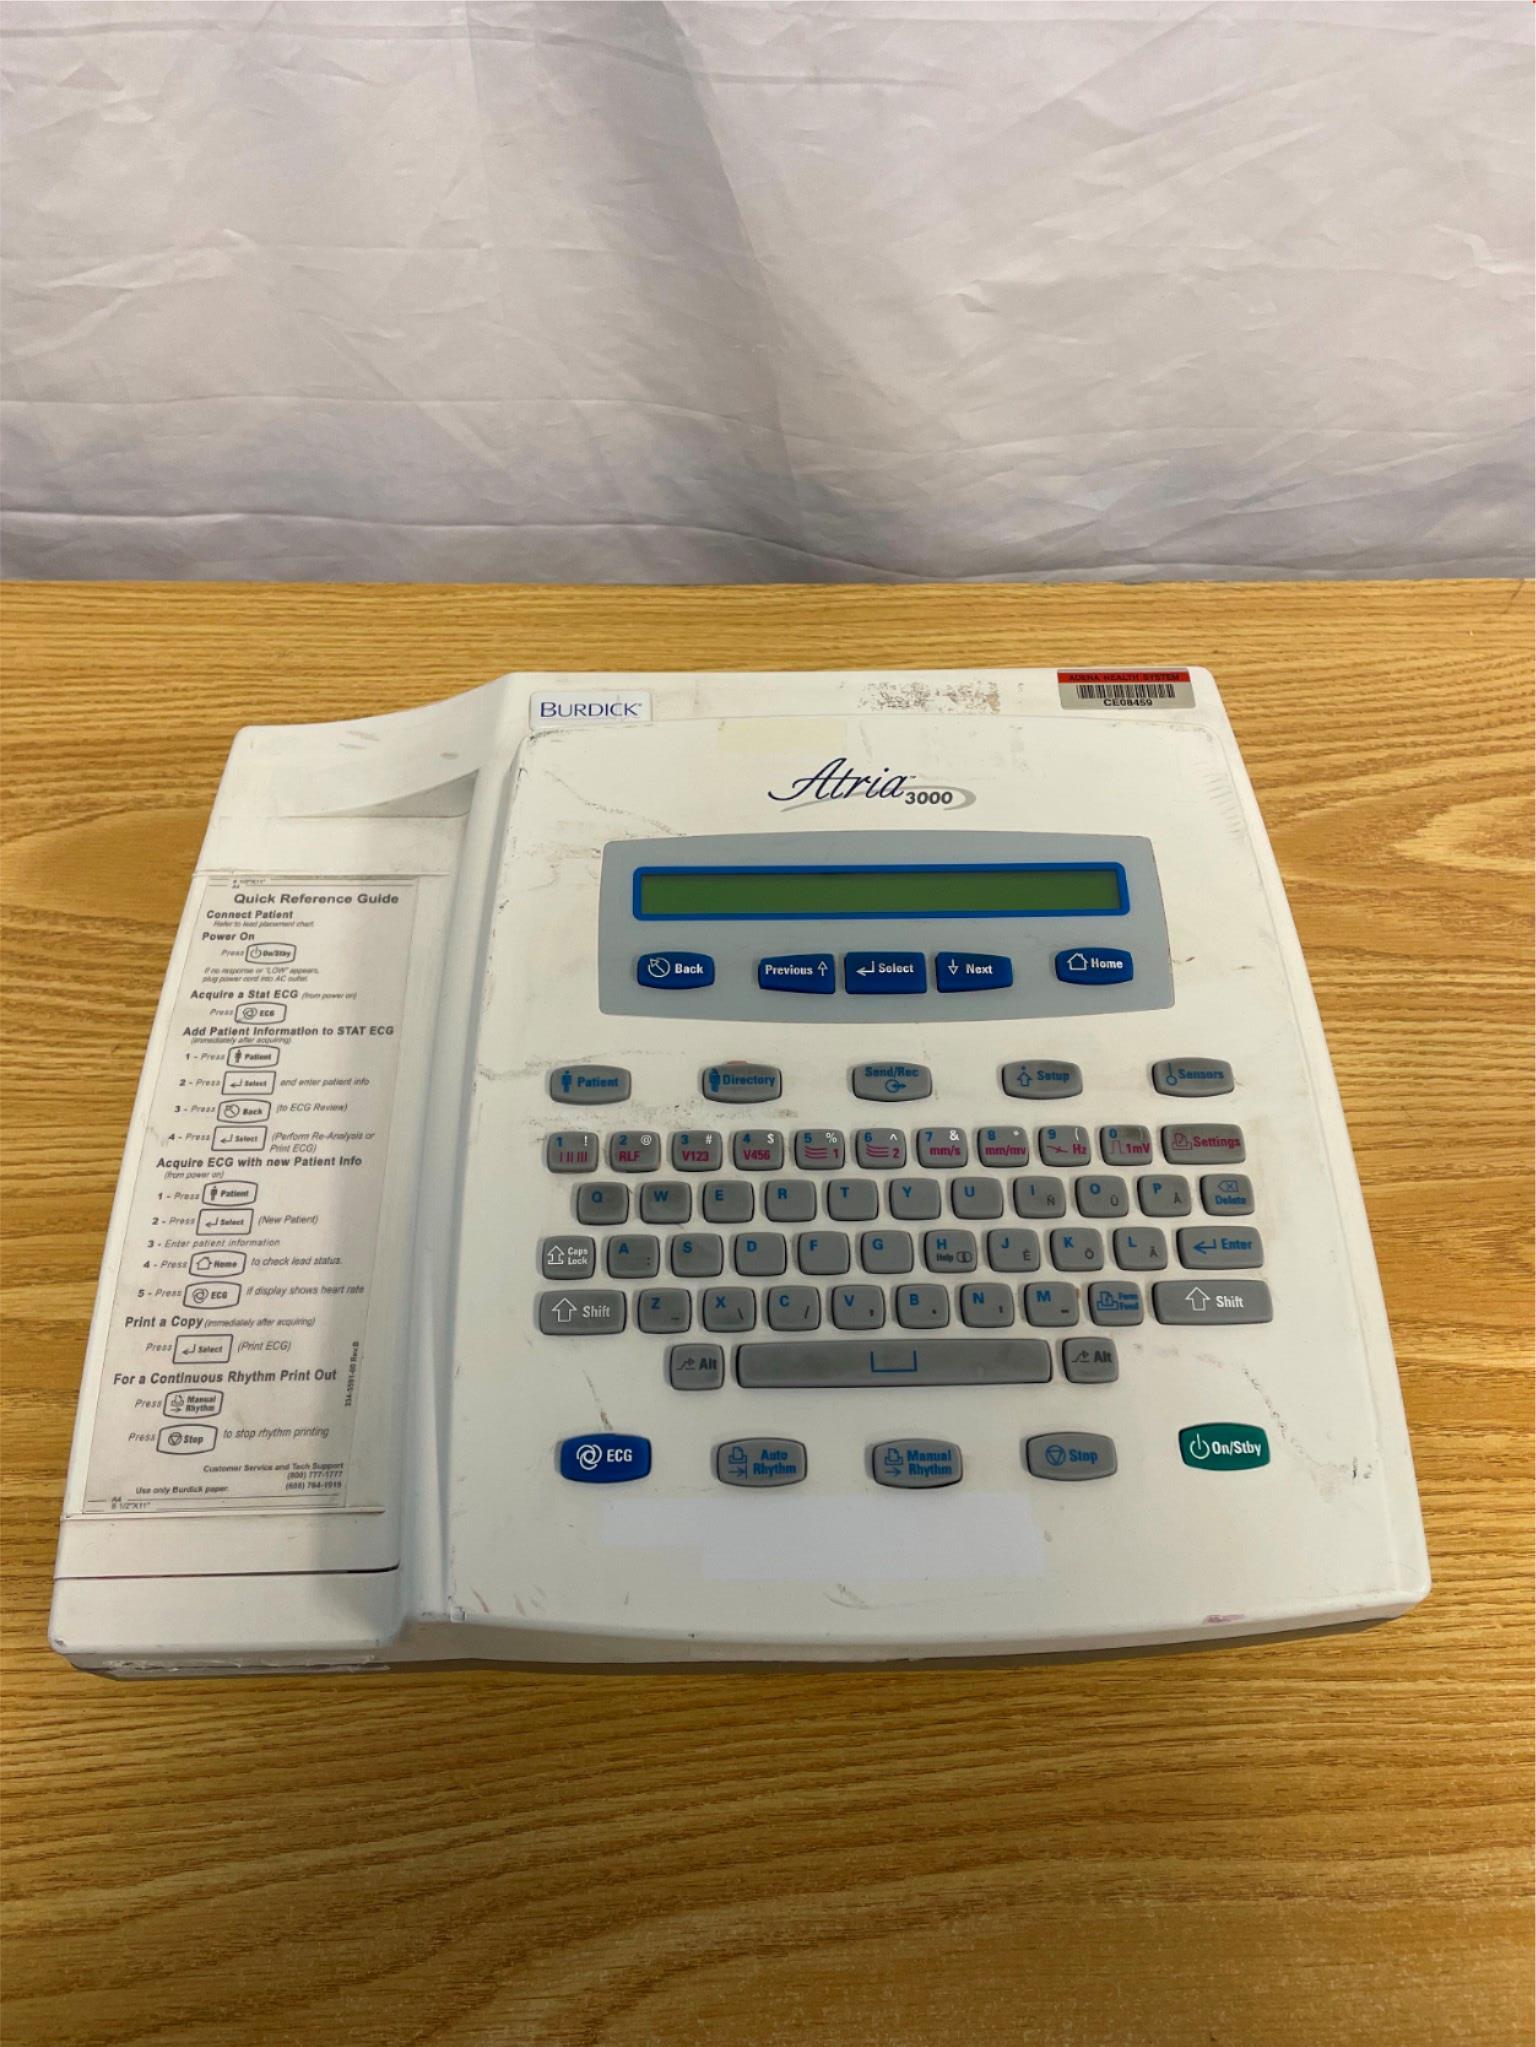

GE APEX PRO CH HANDHELD PATIENT MONITOR APEXPRO

Sale price$ 1,810.80